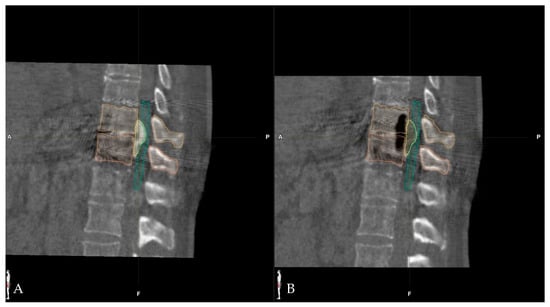

- Pojskić, M.; Bopp, M.; Saß, B.; Kirschbaum, A.; Nimsky, C.; Carl, B. Intraoperative Computed Tomography-Based Navigation with Augmented Reality for Lateral Approaches to the Spine. Brain Sci. 2021, 11, 646. [Google Scholar] [CrossRef] [PubMed]